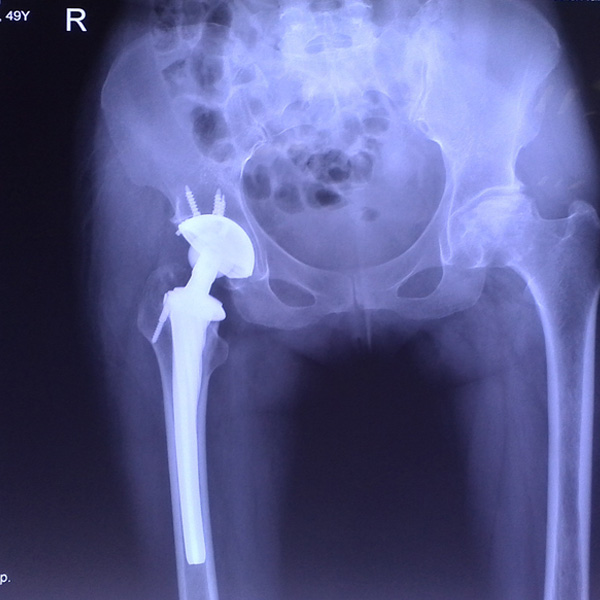

髖關(guān)節(jié)翻修

患者蘇某,女性,11年前因“左髖關(guān)節(jié)屈曲攣縮畸形”行左側(cè)人工全髖關(guān)節(jié)置換,近來感覺左髖關(guān)節(jié)疼痛,不敢行走,經(jīng)“攜生醫(yī)療平臺(tái)”就診于哈......